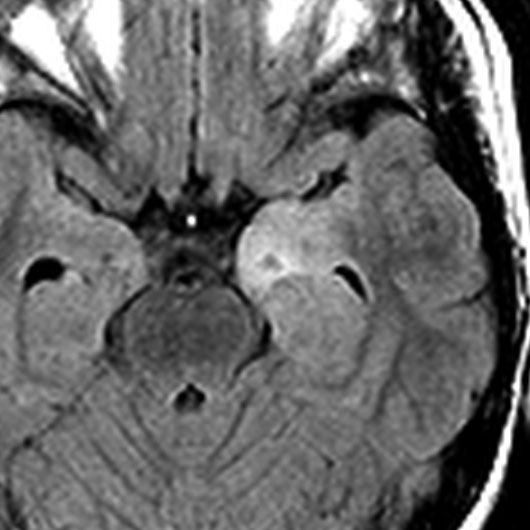

脳幹部から発生した退形成性神経節膠腫 grade 3

軽い右顔面神経麻痺で発症した小児で,右上下肢の軽度の失調症もありました。脳幹部(橋)の右背側から発生した腫瘍で,軽度の閉塞性水頭症を合併しています。左はT2強調画像で,橋の右側ににじむような浸潤像と浮腫があります。腫瘍は小嚢胞を形成してT2強調画像で実質は等信号です。真ん中の画像はCISS画像で橋が腫大しているのがよくわかります。右側はガドリニウム増強像で,全体が増強されてまだらな増強所見となっています。正中後頭下開頭で全摘出 gross total removal して,局所放射線治療とtemozolomide, cisplatine, etoposide, gleevec, hydoreaなどの化学療法を行いましたが,手術後4ヶ月で激しい播種再発を来しました。